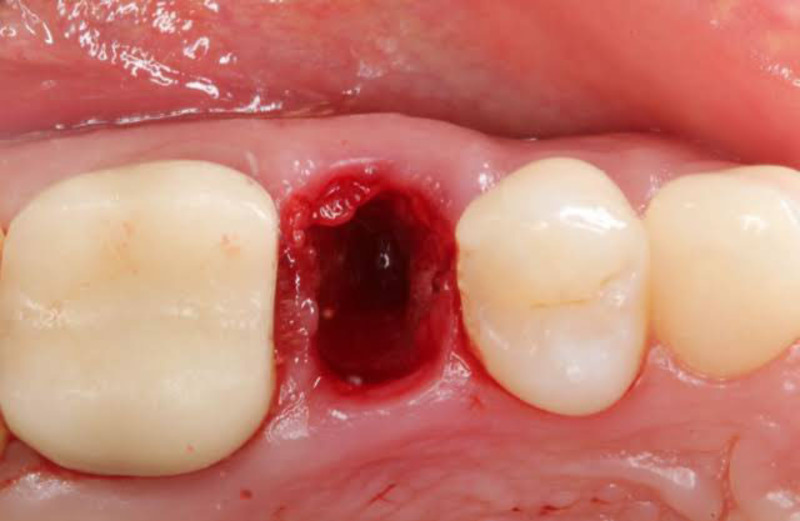

Có lỗ sâu nhẹ trong những ngày đầu: Đây là tình trạng bình thường, đặc biệt nếu nhổ răng khôn hàm dưới hoặc răng có chân lớn. Bên trong lỗ có thể thấy màu đỏ sẫm của cục máu đông hoặc màu trắng vàng nhạt của mô hạt đang lành thương.

Ổ răng sau nhổ răng khôn vẫn còn lỗ hở nhẹ là bình thường